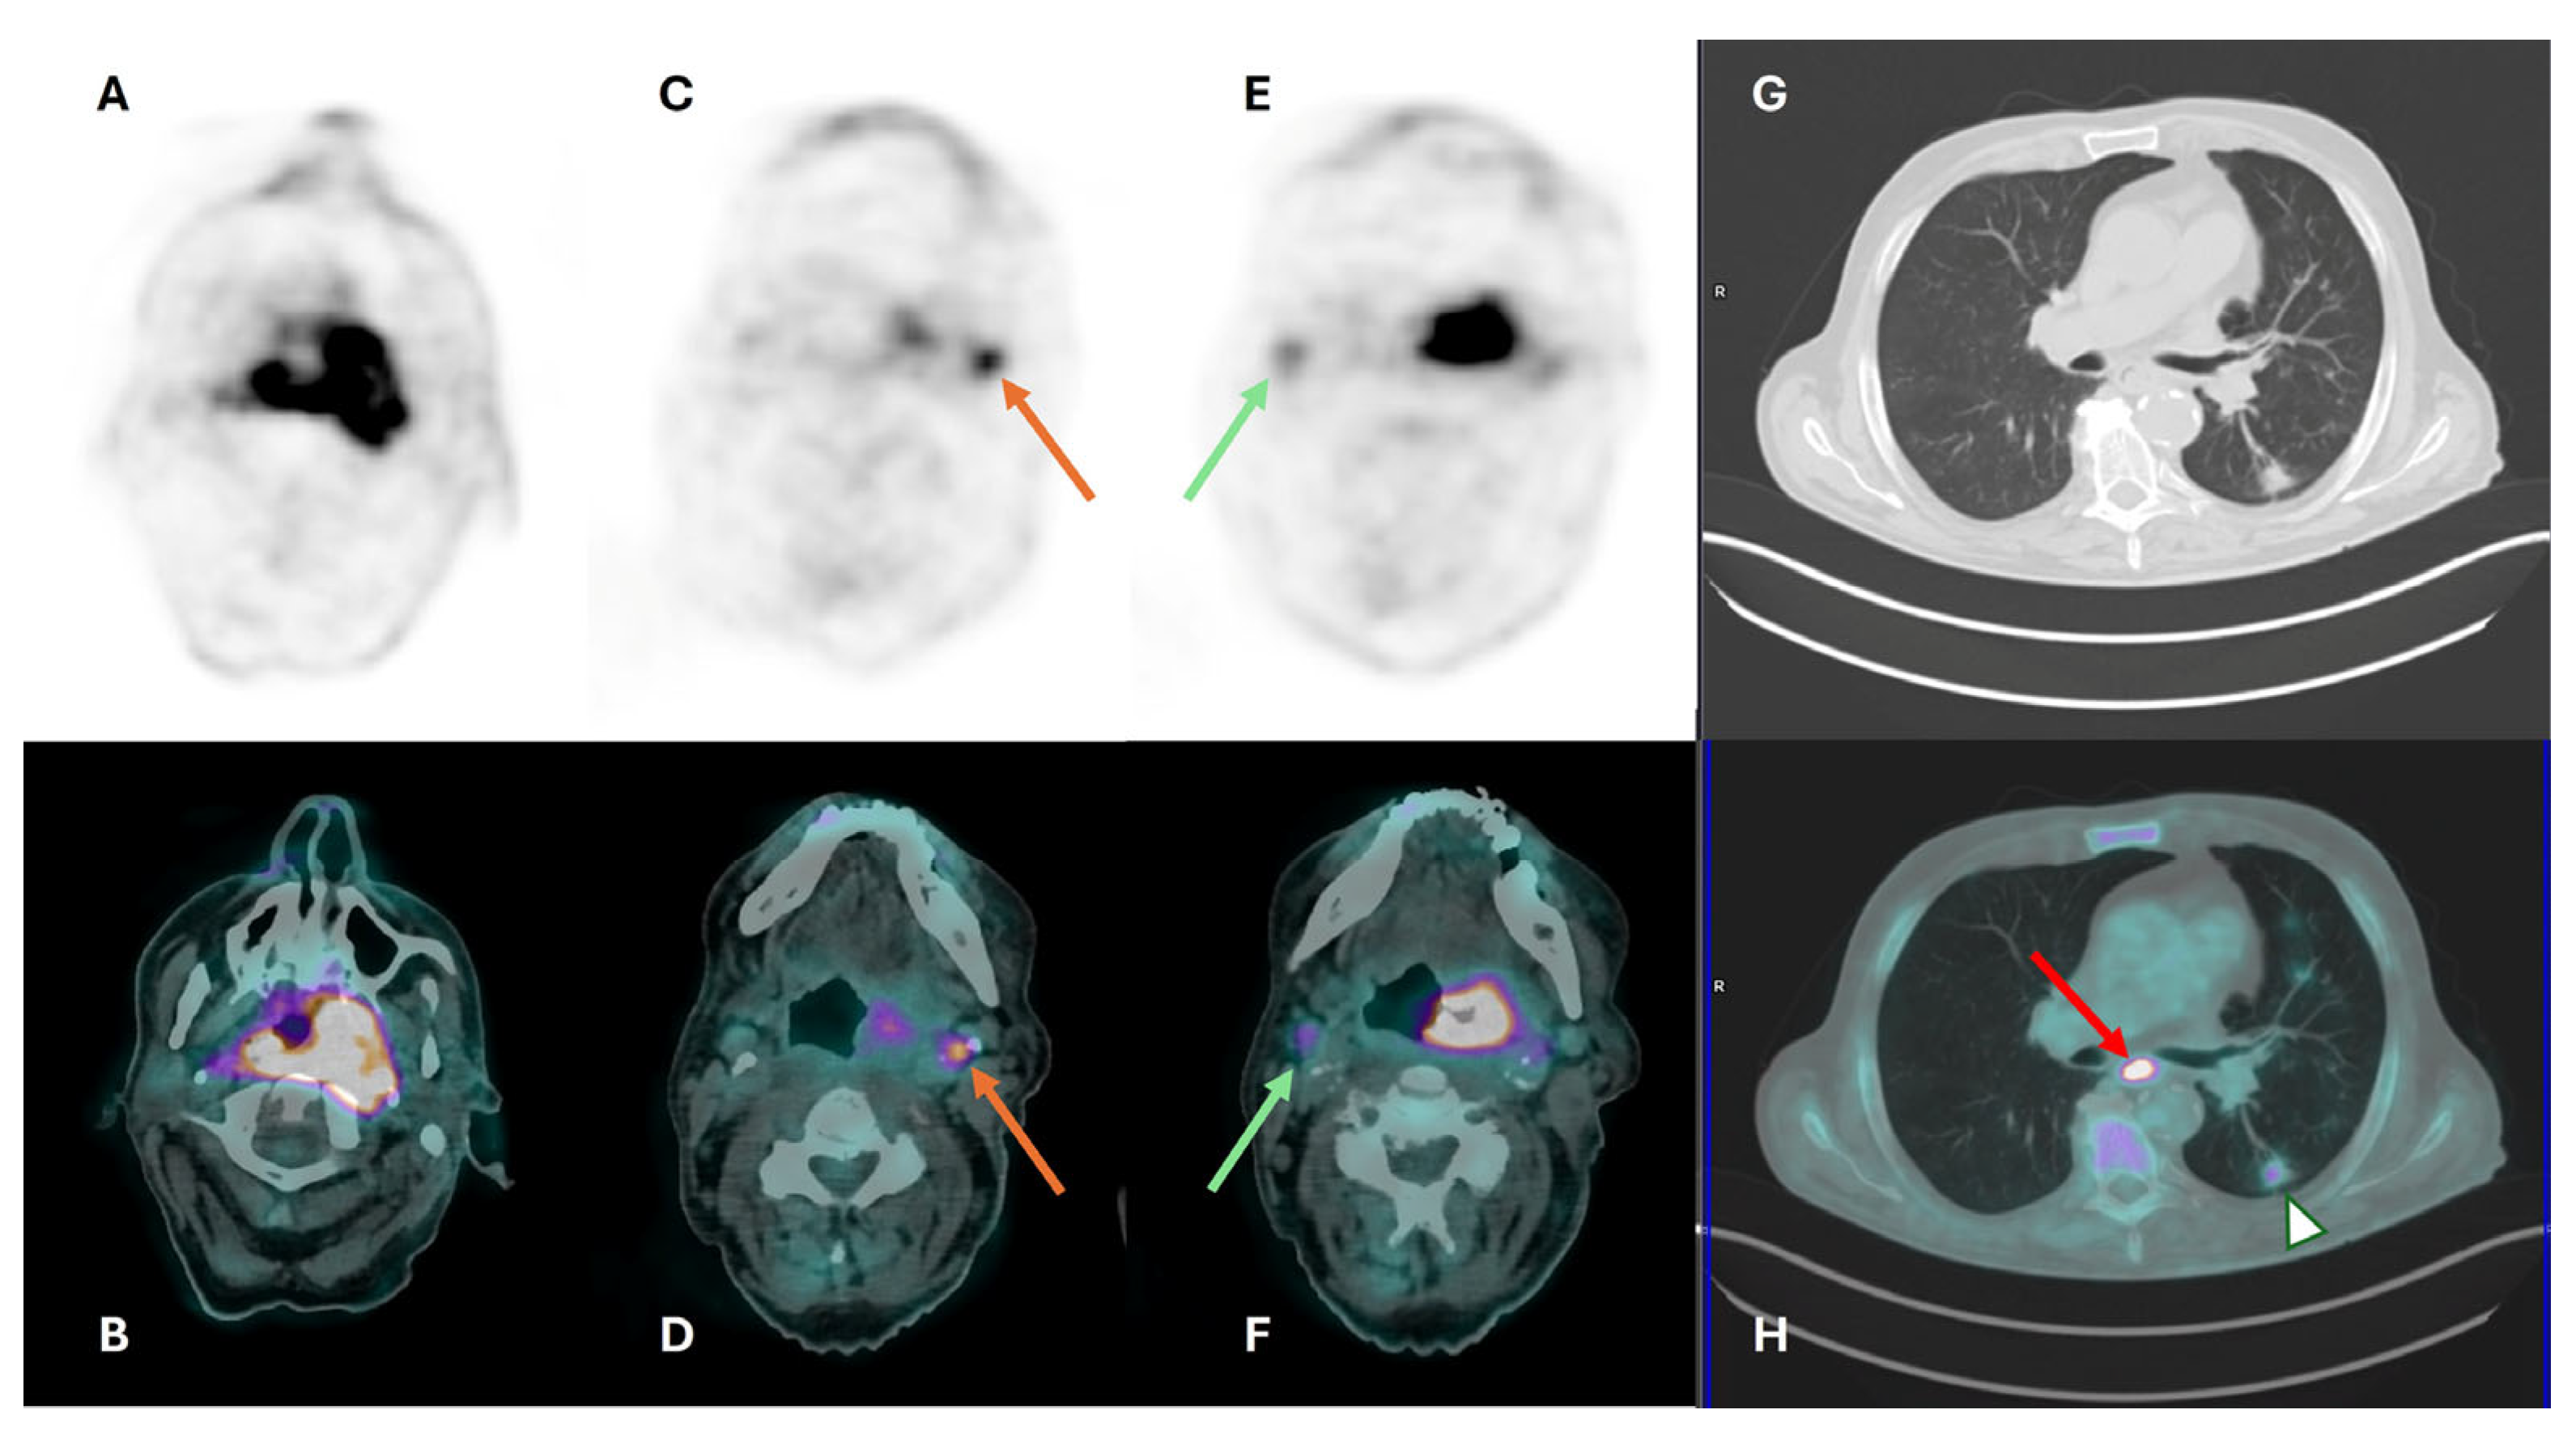

| Selection and delineation of GTV | - Detection of occult primary tumor (see text) - Tumor extension not defined on CT or MRI (see Figure 3) |